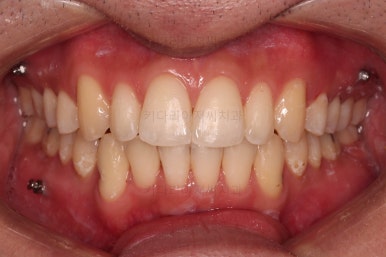

장치를 부착했습니다.

이번 부산연제구교정 환자분이 선택한 장치는 엠파워 클리어라고 하는 자가결찰 세라믹 장치입니다.

최대한 빠른 시일 내에 치열을 가지런하게 해주고 미니스크류를 많이 식립하게 됩니다.

치료시작 6개월 정도 시점의 모습인데, 이정도만 해도 교정이 잘 된 듯 하지만 이제 시작입니다.

얼굴 모습 개선을 위해 해야 될 점들이 많습니다.

미니스크류도 일반적인 위치가 아니라 전반적인 치열의 높낮이를 조절하기에 용이한 위치에 갯수도 매우 많이 식립하게 됩니다.